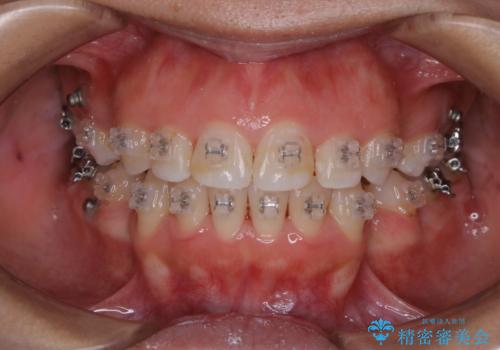

20代女性 ワイヤー矯正中にワイヤーを外してきれいにクリーニンング

担当医 歯科衛生士